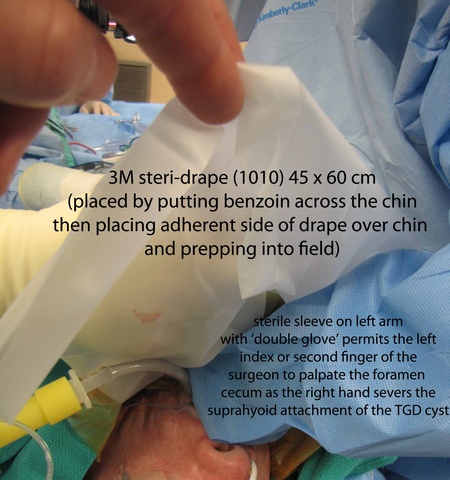

After written informed consent was obtained with a history and physical reviewed along with a brief 'time out', the patient was placed under general anesthesia with endotracheal intubation with a 6.0 MLT tube. The patient was positioned with the back-elevated, neck extended position with the head toward anesthesia. Benzoin was placed across the chin and a 1010 drape placed with adherent (sticky) portion applied to benzoined region with remained draped over mouth to permit later access to oral cavity.

From above, surgeon reached into the mouth and palpated the foramen cecum with the left hand and arm protected with a sterile sleeve and second glove - placed to permit later removal from the contaminated oral cavity to permit continued sterile dissection in a sterile field. With anatomic control directed by palpation intra-orally with concurrent dissection of the open neck, clips were placed to mark the region of the undersurface of the base of tongue where the TGD cyst was to be severed. Final cuts with the bovie were similarly directed both by intra-oral palpation and extra-oral inspection.